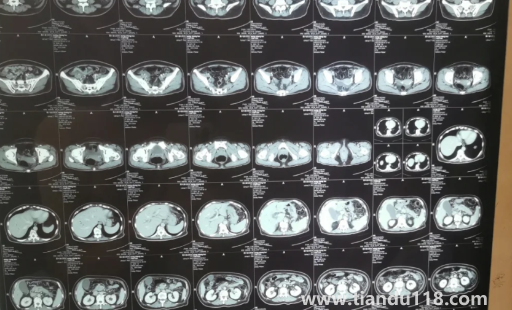

胰腺不舒服早期大便會(huì)變化嗎(胰腺有問(wèn)題會(huì)不會(huì)打嗝)

胰腺不舒服早期其實(shí)變化并是很大,根本就看不出來(lái),所以有人才會(huì)說(shuō)胰腺被查出后是很難醫(yī)治的,是癌癥之中最令人害怕的。那么,胰腺不舒服早期胰腺炎注意哪些飲食呢?一起來(lái)看看天都生活網(wǎng)帶來(lái)的詳細(xì)介紹吧!